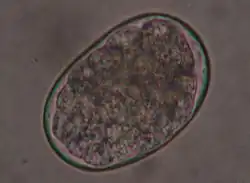

T. canis eggs

T. canis is an 8 to 18 cm long nematode that parasitizes (lives as a parasite) in the small intestine. There, the adult females release approximately 85 μm large unfurrowed eggs, whose shell is thick and rough (golf ball-like) and which are released into the outside world via the feces. The period from infection to egg laying (prepatency) is three to six weeks, depending on the route of infection and the age of the dog. T. canis does not require an intermediate host for development, but infection of dogs can occur via collective hosts such as rodents and birds. In collective hosts (paratenic hosts), no complete development cycle of the parasites occurs, but infective stages can accumulate in them through multiple infections. In principle, three routes of infection are possible for T. canis: peroral infection and transplacental and galactogenic infection, which are much more common in puppies.